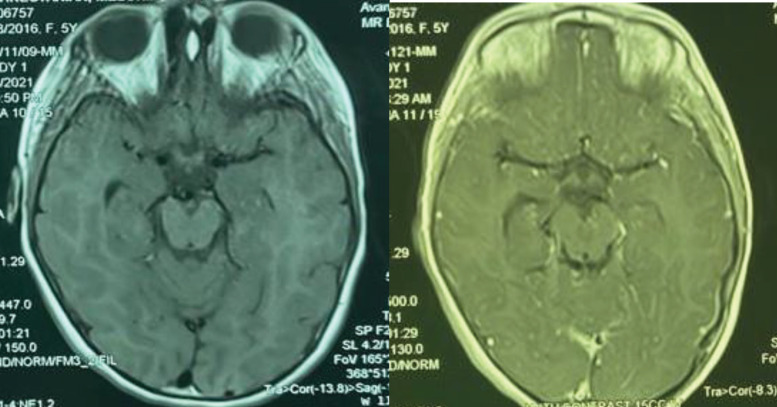

Brown-Vialetto-Van Laere syndrome (BVVLS) is a rare neurodegenerative disorder of childhood. According to the previous reports, it has various primary signs and symptoms. Because of the simple treatment with riboflavin supplementation, it is important to have suspicious to this disease and begin treatment even before genetic test confirm. We report a five-year-old girl with BVVLS that manifest with hearing problems, first. There was obvious improvement in her disease clinical signs with riboflavin supplementation treatment.

Abstract Image